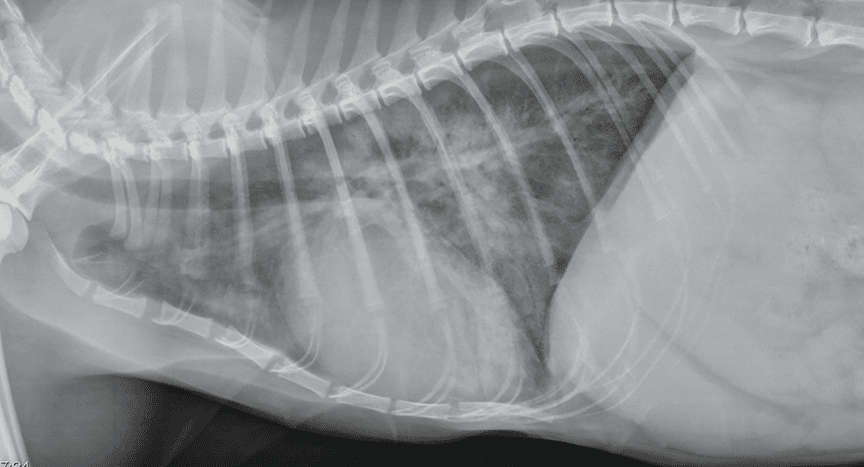

Chẩn đoán phù phổi không do tim ở chó mèo

Chẩn đoán thường dựa trên sự kết hợp của nhiều yếu tố:

-

Khám lâm sàng và đánh giá tình trạng hô hấp

Khai thác tiền sử stress, chấn thương hoặc nhiễm trùng

Chụp X-quang ngực khi tình trạng cho phép

Đánh giá tim mạch để loại trừ nguyên nhân do tim